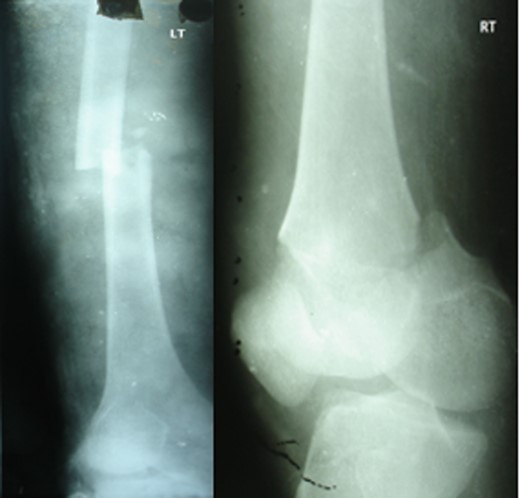

Blood parameters were within normal limits. X-ray of the pelvis revealed a right posterior hip dislocation with Pipkins's type II fracture (Rt) and ipsilateral distal medial condylar fracture with a fracture shaft of femur (Lt) (Figs 1 and 2). A CT scan confirmed the infrafoveal right-sided Pipkin's-II fracture of the femoral head (Fig. 3). A nerve conduction velocity study of lower limb suggested neuropraxia of sciatic nerve. Following attempt of closed reduction, CT scan and X-rays revealed incongruous reduction.

Initial X-ray: left thigh (anteroposterior view) and right knee (oblique view).